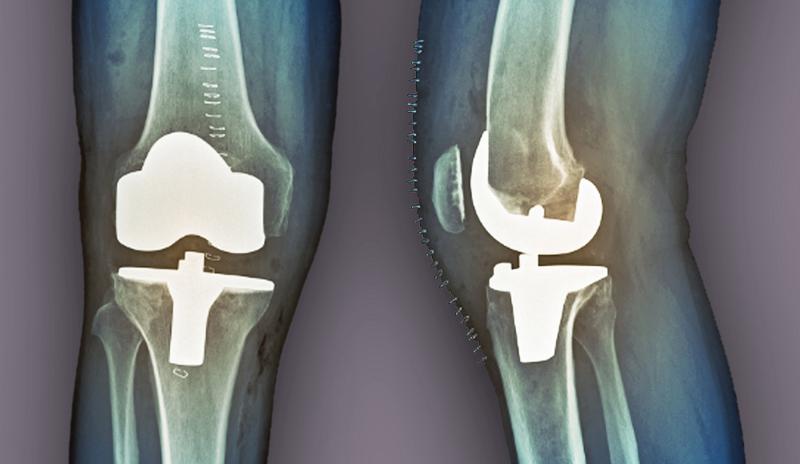

Tanınma Süreci Diz kapağı burkulması tanısı, genellikle fiziksel muayene ve görüntüleme yöntemleri ile konur. Doktor, hastanın tıbbi öyküsünü alır ve dizin durumunu değerlendirir. Ayrıca, burkulmanın derecesini belirlemek için aşağıdaki yöntemler kullanılabilir: